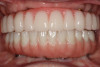

Fig 20. Patient smiling with his definitive prostheses.v

Figure 20